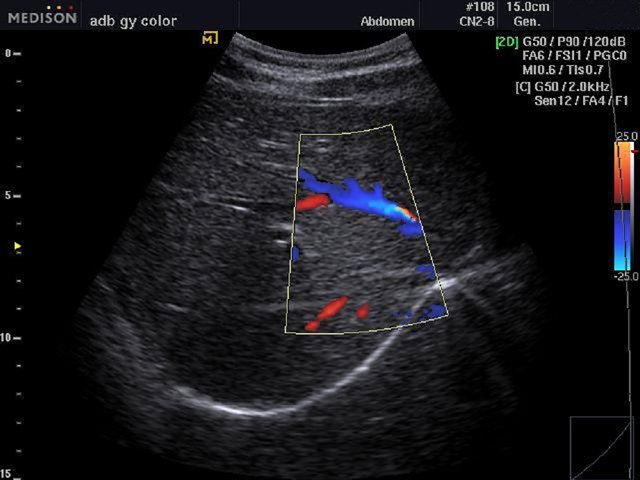

[EN] Эхограмма №483: Кровоток в печени, режим цветного допплеровского картирования (конвексный датчик 2-8 МГц).

Изображение получено с помощью УЗ аппарата SonoAce-R3 (снят с производства).